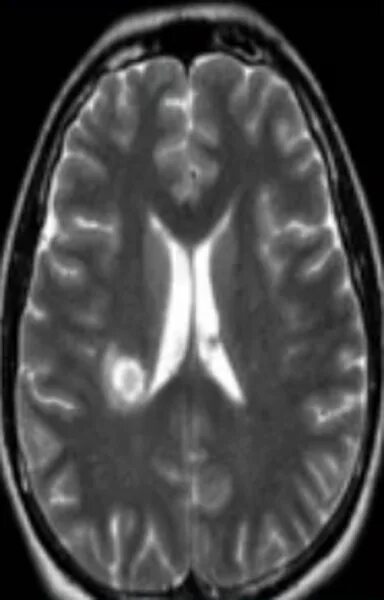

Очаг глиоза в теменной доле